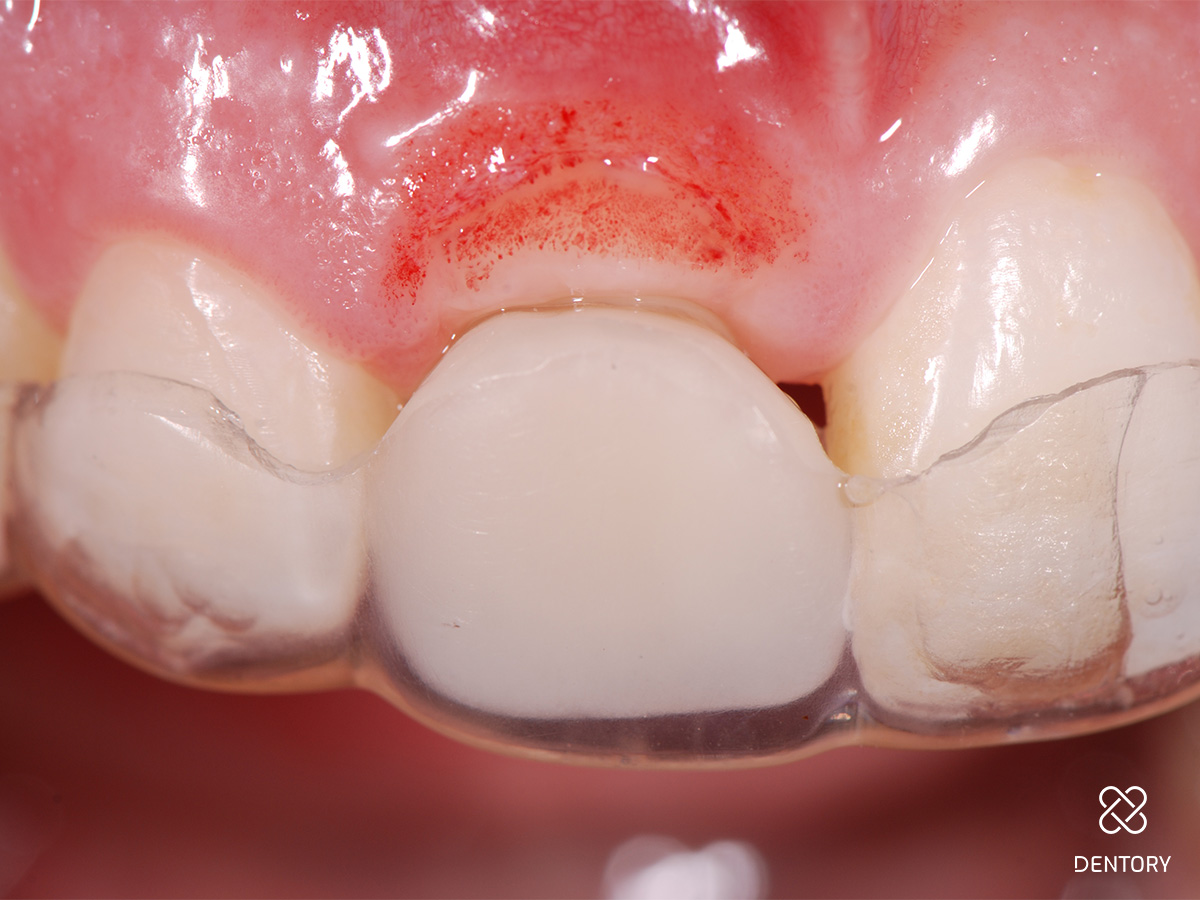

Abbildung 12

Provisorische Versorgung mit einer Tiefziehschiene; alternativ kann auch eine kleine Prothese oder eine Klebebrücke verwendet werden.